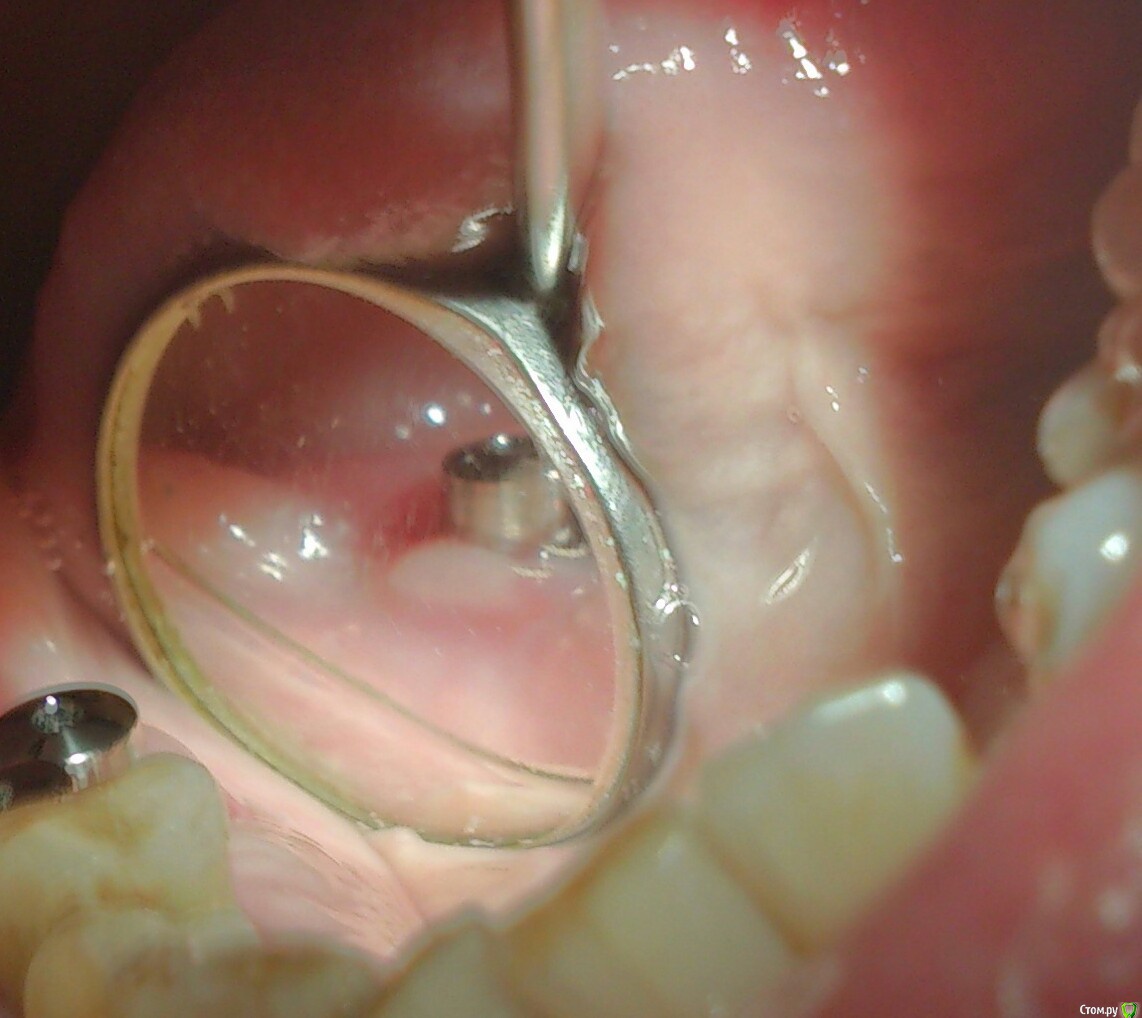

andrey_1965 Опубликовано 21 декабря, 2015 Поделиться Опубликовано 21 декабря, 2015 Ну как результат ?1.-диэпителизация подворот лоскута очень удобно,но опасно для резбы через неделю.язычно-механическая травма через 10 дней через 3недели. На временных доформирую рельеф.2. вроде ничего нештатного через 2недели A-PRF через 5недель убрал все,закрыл мембраной A-PRF две поперек,одна в доль через неделю через 13дней через 21день. Следующий осмотр будет на сроке 5 недель(думаю все сравняется) 3. через неделю 2недели 3недели,на дистальных отмываю помойку4 недели Ссылка на комментарий